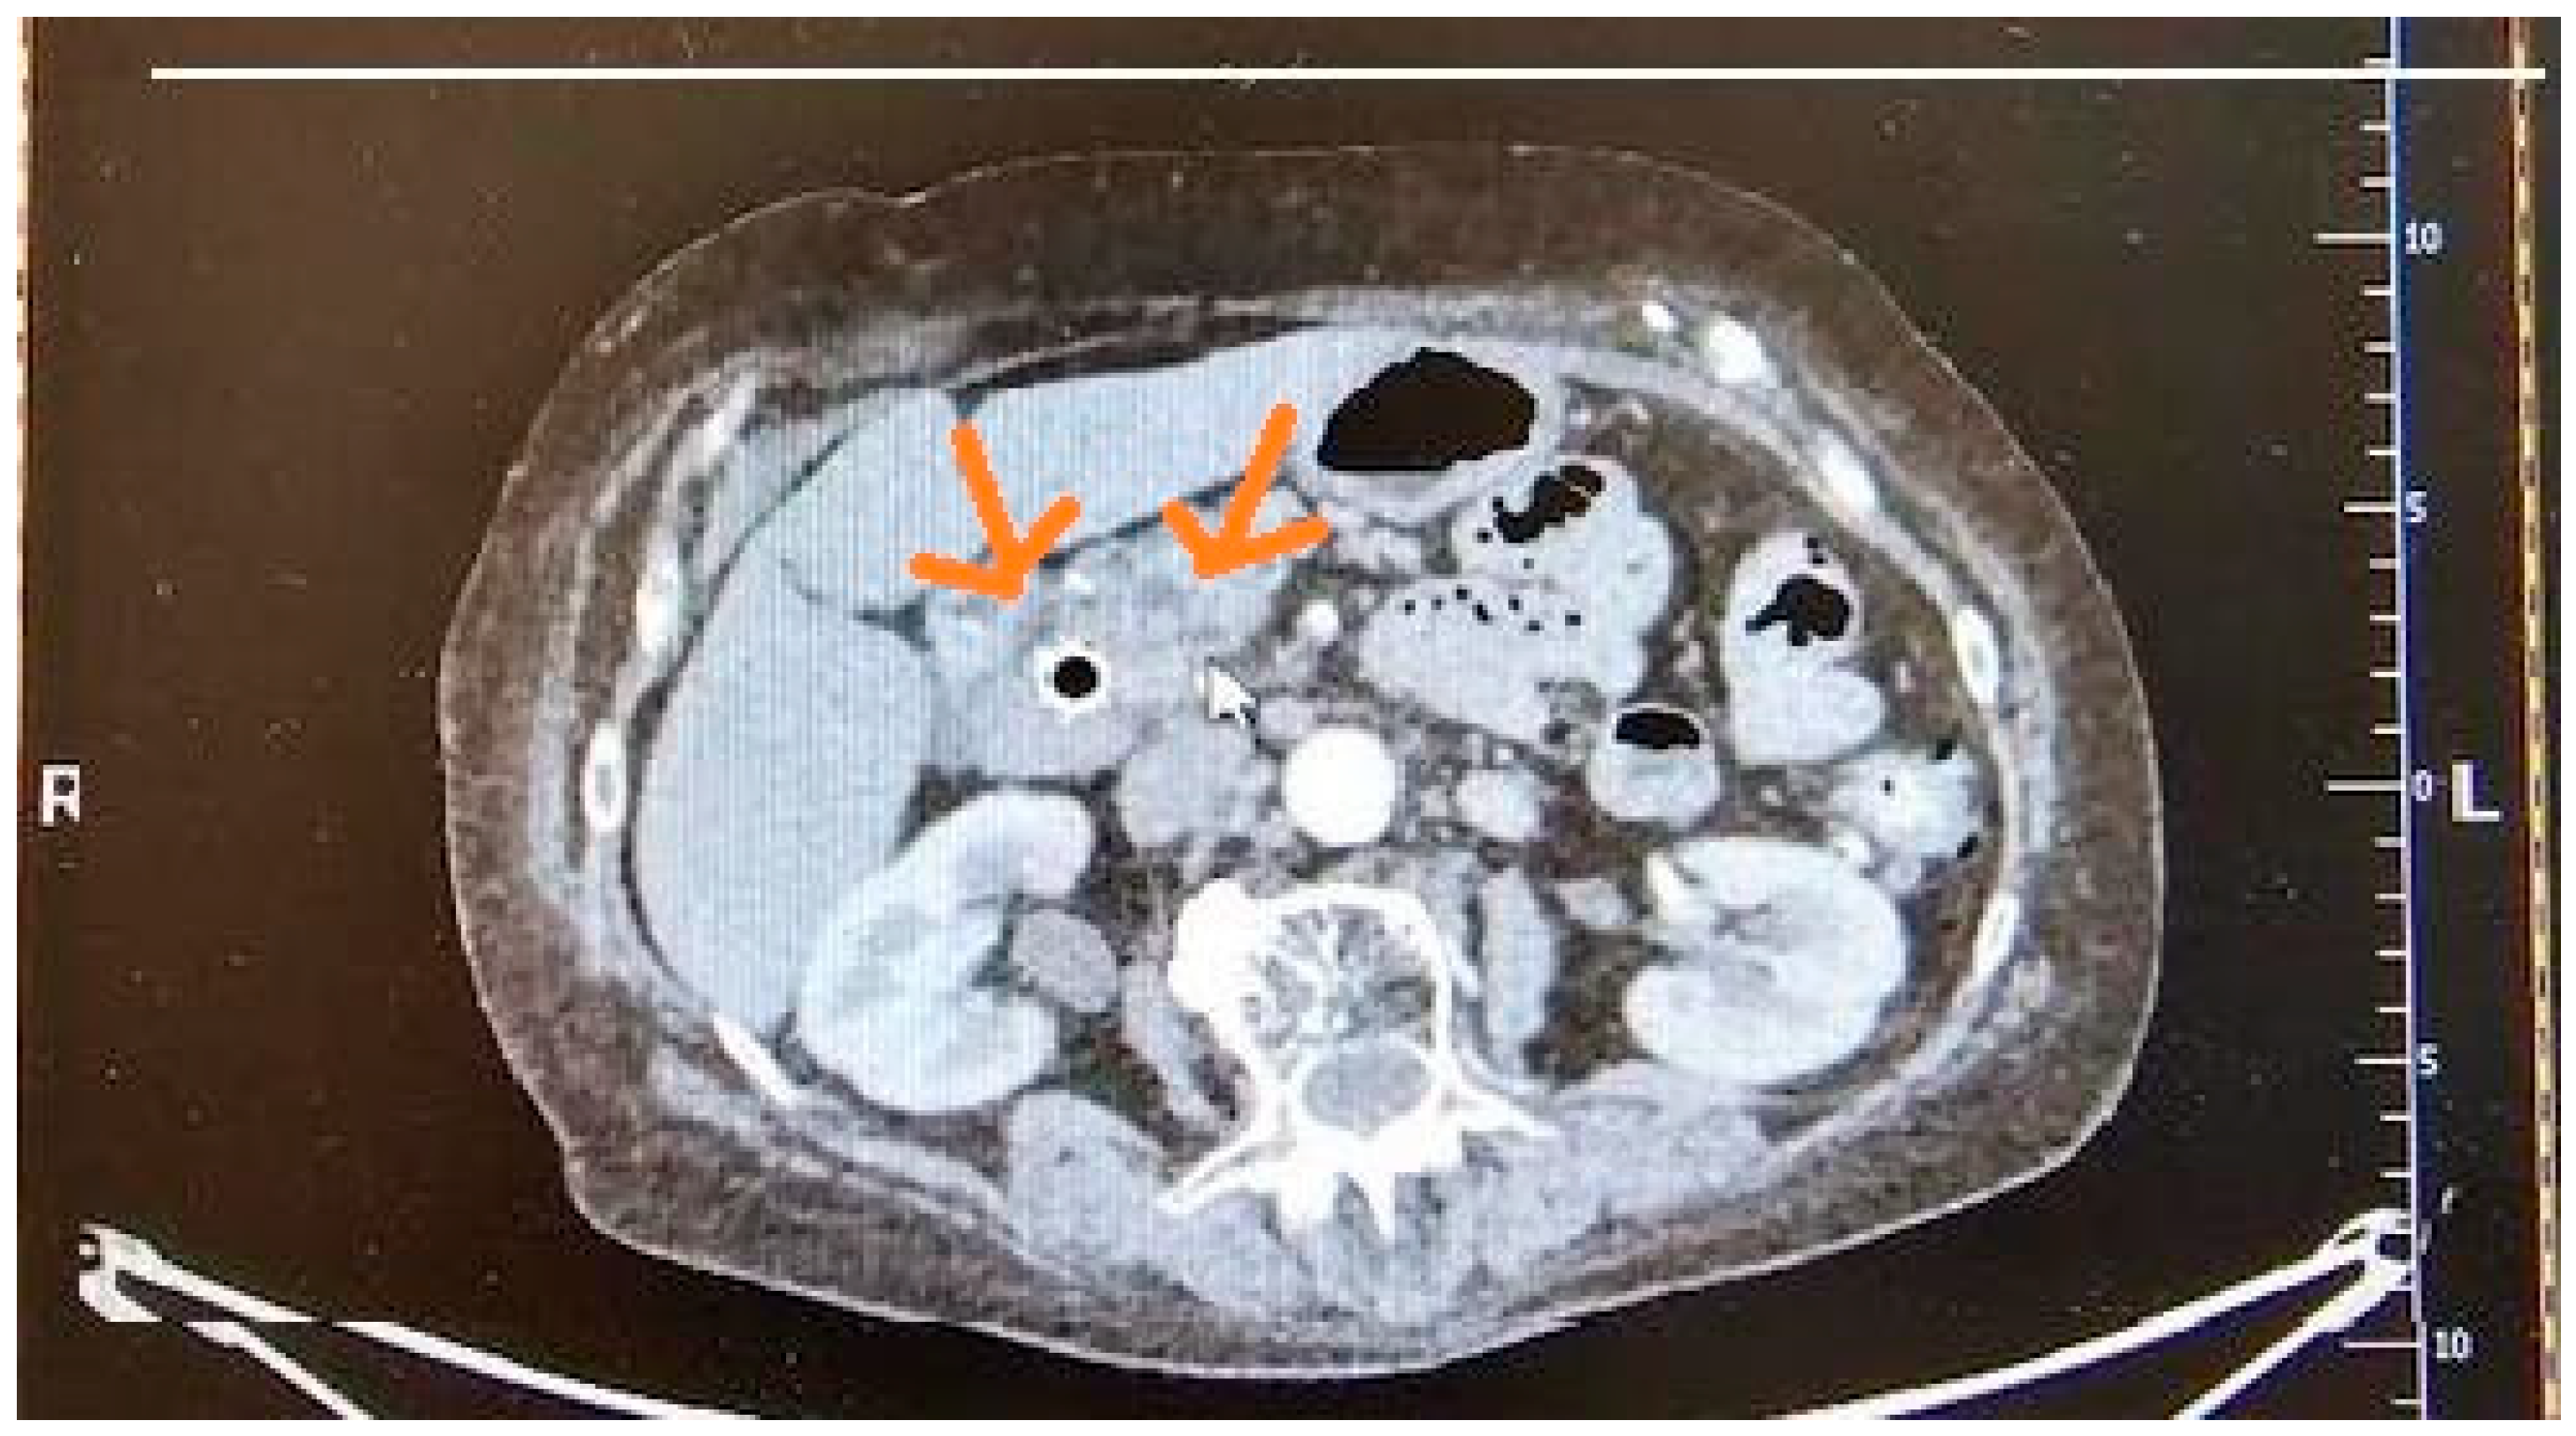

3.2. Computed Tomography (CT)

10.2. Computed Tomography (CT)